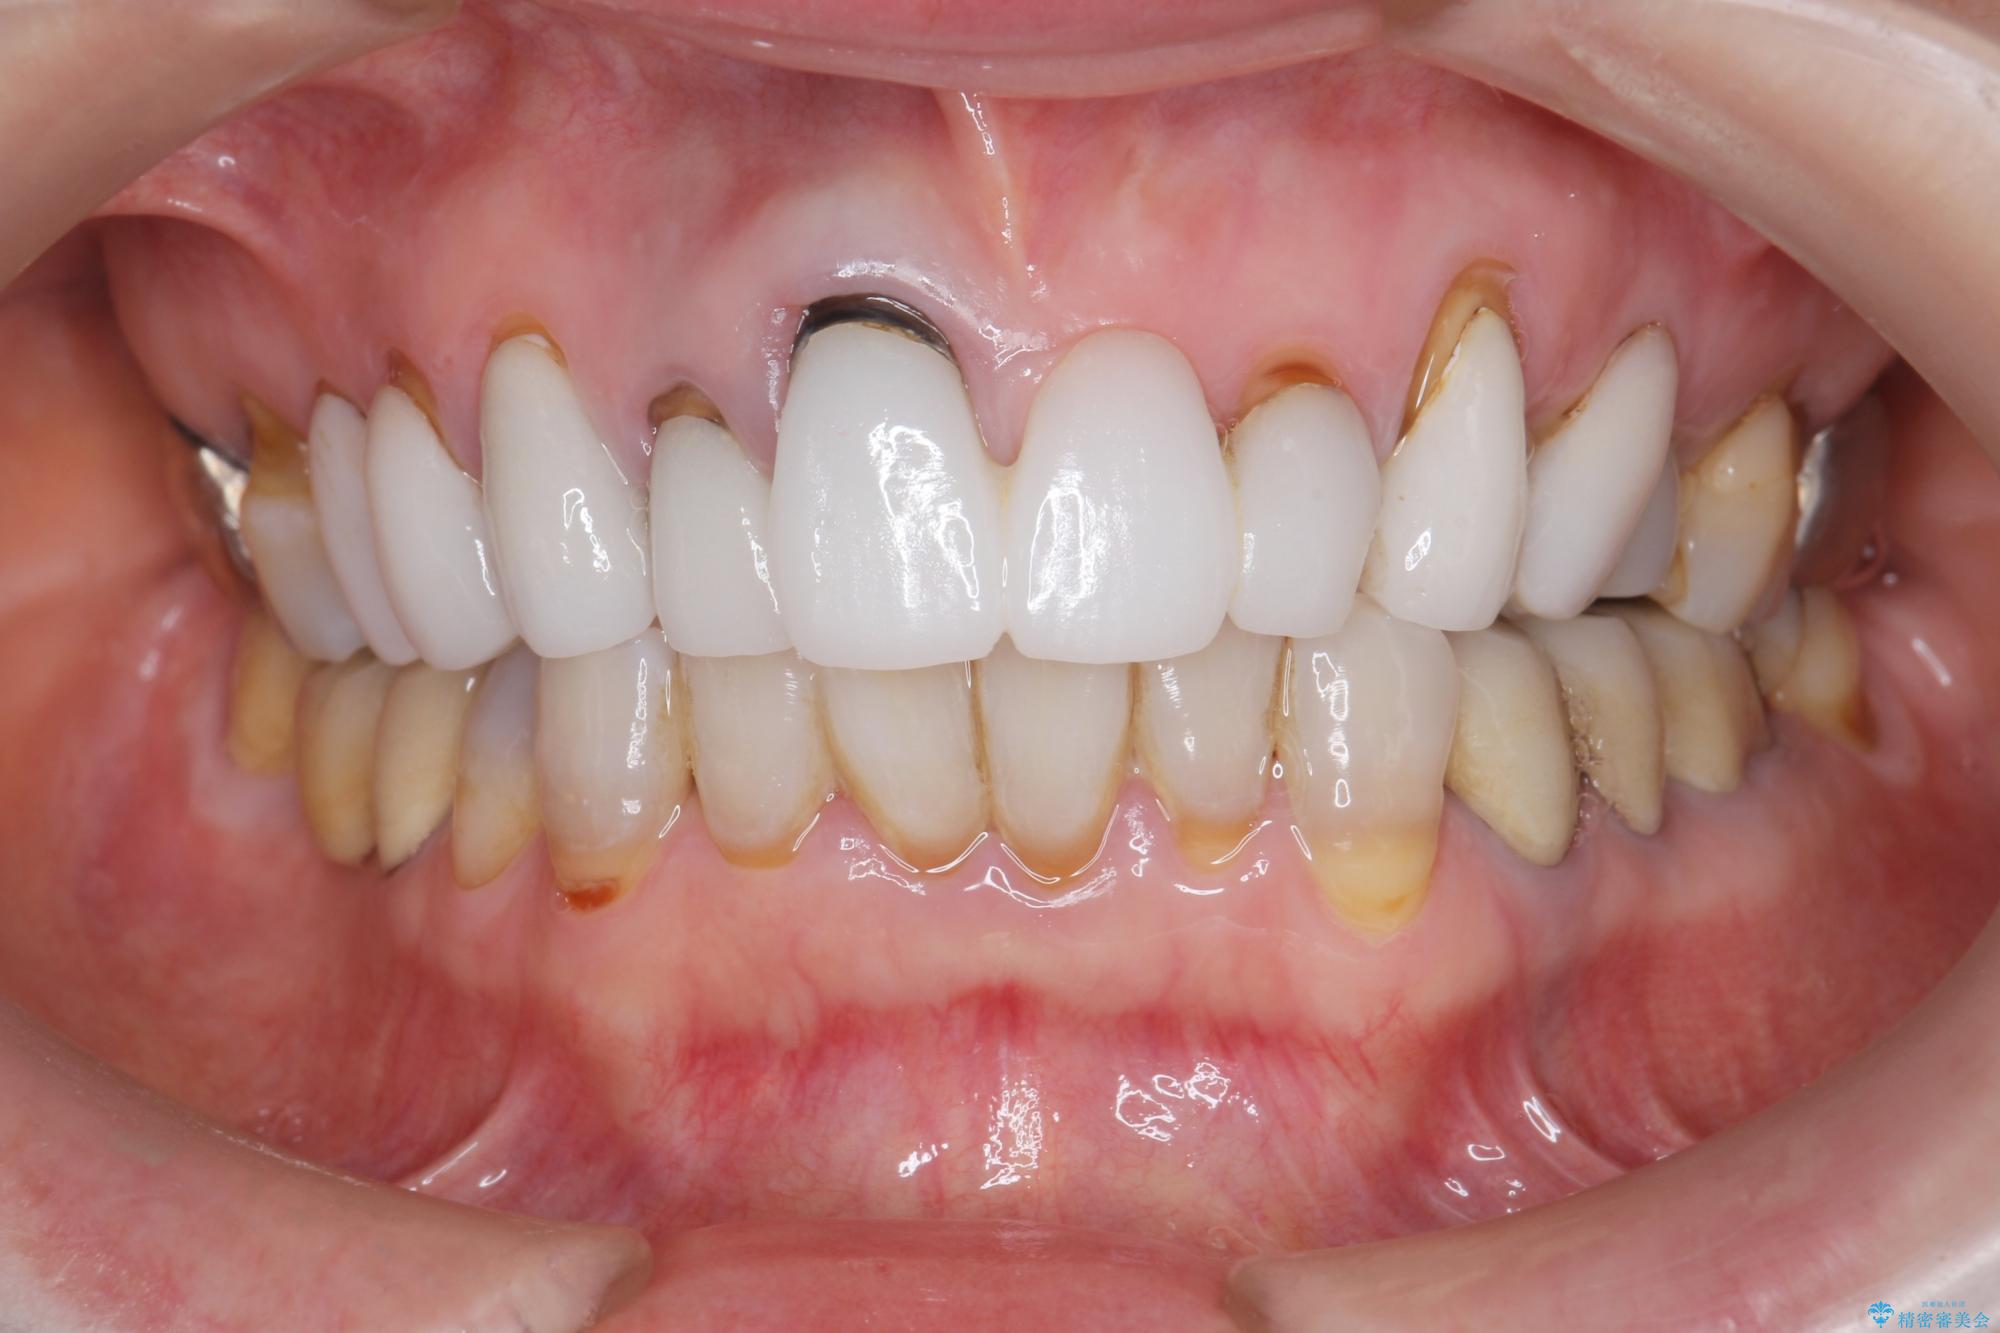

[ セラミック治療 ] 歯ぐきの際の黒ずみを改善したい

- 歯ぐきとセラミックの間の黒ずみが目立つので、きれいに治してほしい。と希望され来院されました。

歯ぐきの位置が変化しクラウン下の歯が見えるようになってしまったことで、審美障害が生じている状態です。

クラウンマージンの再設定を行うことで、黒ずんだ部分を再度覆い、審美障害を改善します。

- 52.8万円(ジルコニアクラウン×4・仮歯×4)費用は治療当時の料金となります